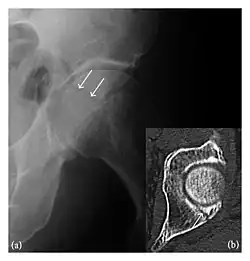

High-energy trauma fractures

Occult osseous injuries may result from a direct blow to the bone by compressive forces of adjacent bones against one another or by traction forces during an avulsion injury. Lesions in the tibial plateau, hip, ankle, and wrist are often missed. In a tibial plateau fracture, any disruption of the posterior and anterior cortical rims of the plateau should be sought. Impaction of subchondral bone will appear as an increased sclerosis of the subchondral bone (Figure 1). In the hip, posterior acetabular fractures also present subtle radiographic findings. The acetabular lines should then be carefully examined keeping in mind that the posterior rim, which is harder to see on X-rays, is more frequently fractured than the anterior rim (Figure 2). In the wrist, detection of carpal bone fractures is often challenging, with up to 18% of scaphoid fractures radiographically occult. Carpal fractures, especially the scaphoid, are associated with the risk of avascular necrosis. In apparently normal wrist radiographs from symptomatic patients, if there is history of a fall on an outstretched hand with pain in the anatomic snuffbox, suggesting scaphoid injury, the initial examination with posteroanterior, lateral, and pronation oblique views must be complemented by other specific views such as supination oblique and the "scaphoid" view A careful examination of cortices for evidence of discontinuity or offset and cancellous bone for lucency is necessary (Figure 3).[1]

The greater tuberosity of the humerus is also an illustrative location of occult fractures. The osseous injury may follow seizures, glenohumeral dislocation, forced abduction, or direct impaction. They are commonly discovered on MRI in symptomatic patients with suspicion of rotator cuff tear. Coronal images are best suited for detection. They appear as crescentic oblique lines surrounded by a bone marrow edema pattern (Figure 5). The rotator cuff must be inspected since associated ligamentous lesions are common. In the ankle, malleoli and tarsal bones should be checked carefully for any cortical disruptions and radiolucent lines that may reveal a fracture. Awareness of the exact location of the pain will help direct the attention of the interpreter when searching for very subtle signs of fracture (Figure 6).[1]

a

b

Figure 6: Subtle anterior talar fracture in a 39-year-old man presenting with ankle pain after a fall. (a) Anteroposterior radiograph shows a subtle oblique radiolucent line through the talus (white arrows). (b) Sagittal CT reformation confirms the presence of an anterior talar fracture with cortical offset (black arrow). Avulsion fractures, which consist of a detached bone fragment resulting from a ligament or tendon pulling away from the bone, may also present with subtle radiographic signs. Tiny osseous fragments near the presumed attachment site of a ligament suggest this diagnosis. Common sites are the lateral tibial plateau (the Segond fracture), the spinal tuberosity of the tibia resulting from anterior cruciate ligament avulsion, and the ischial tuberosity.[1]